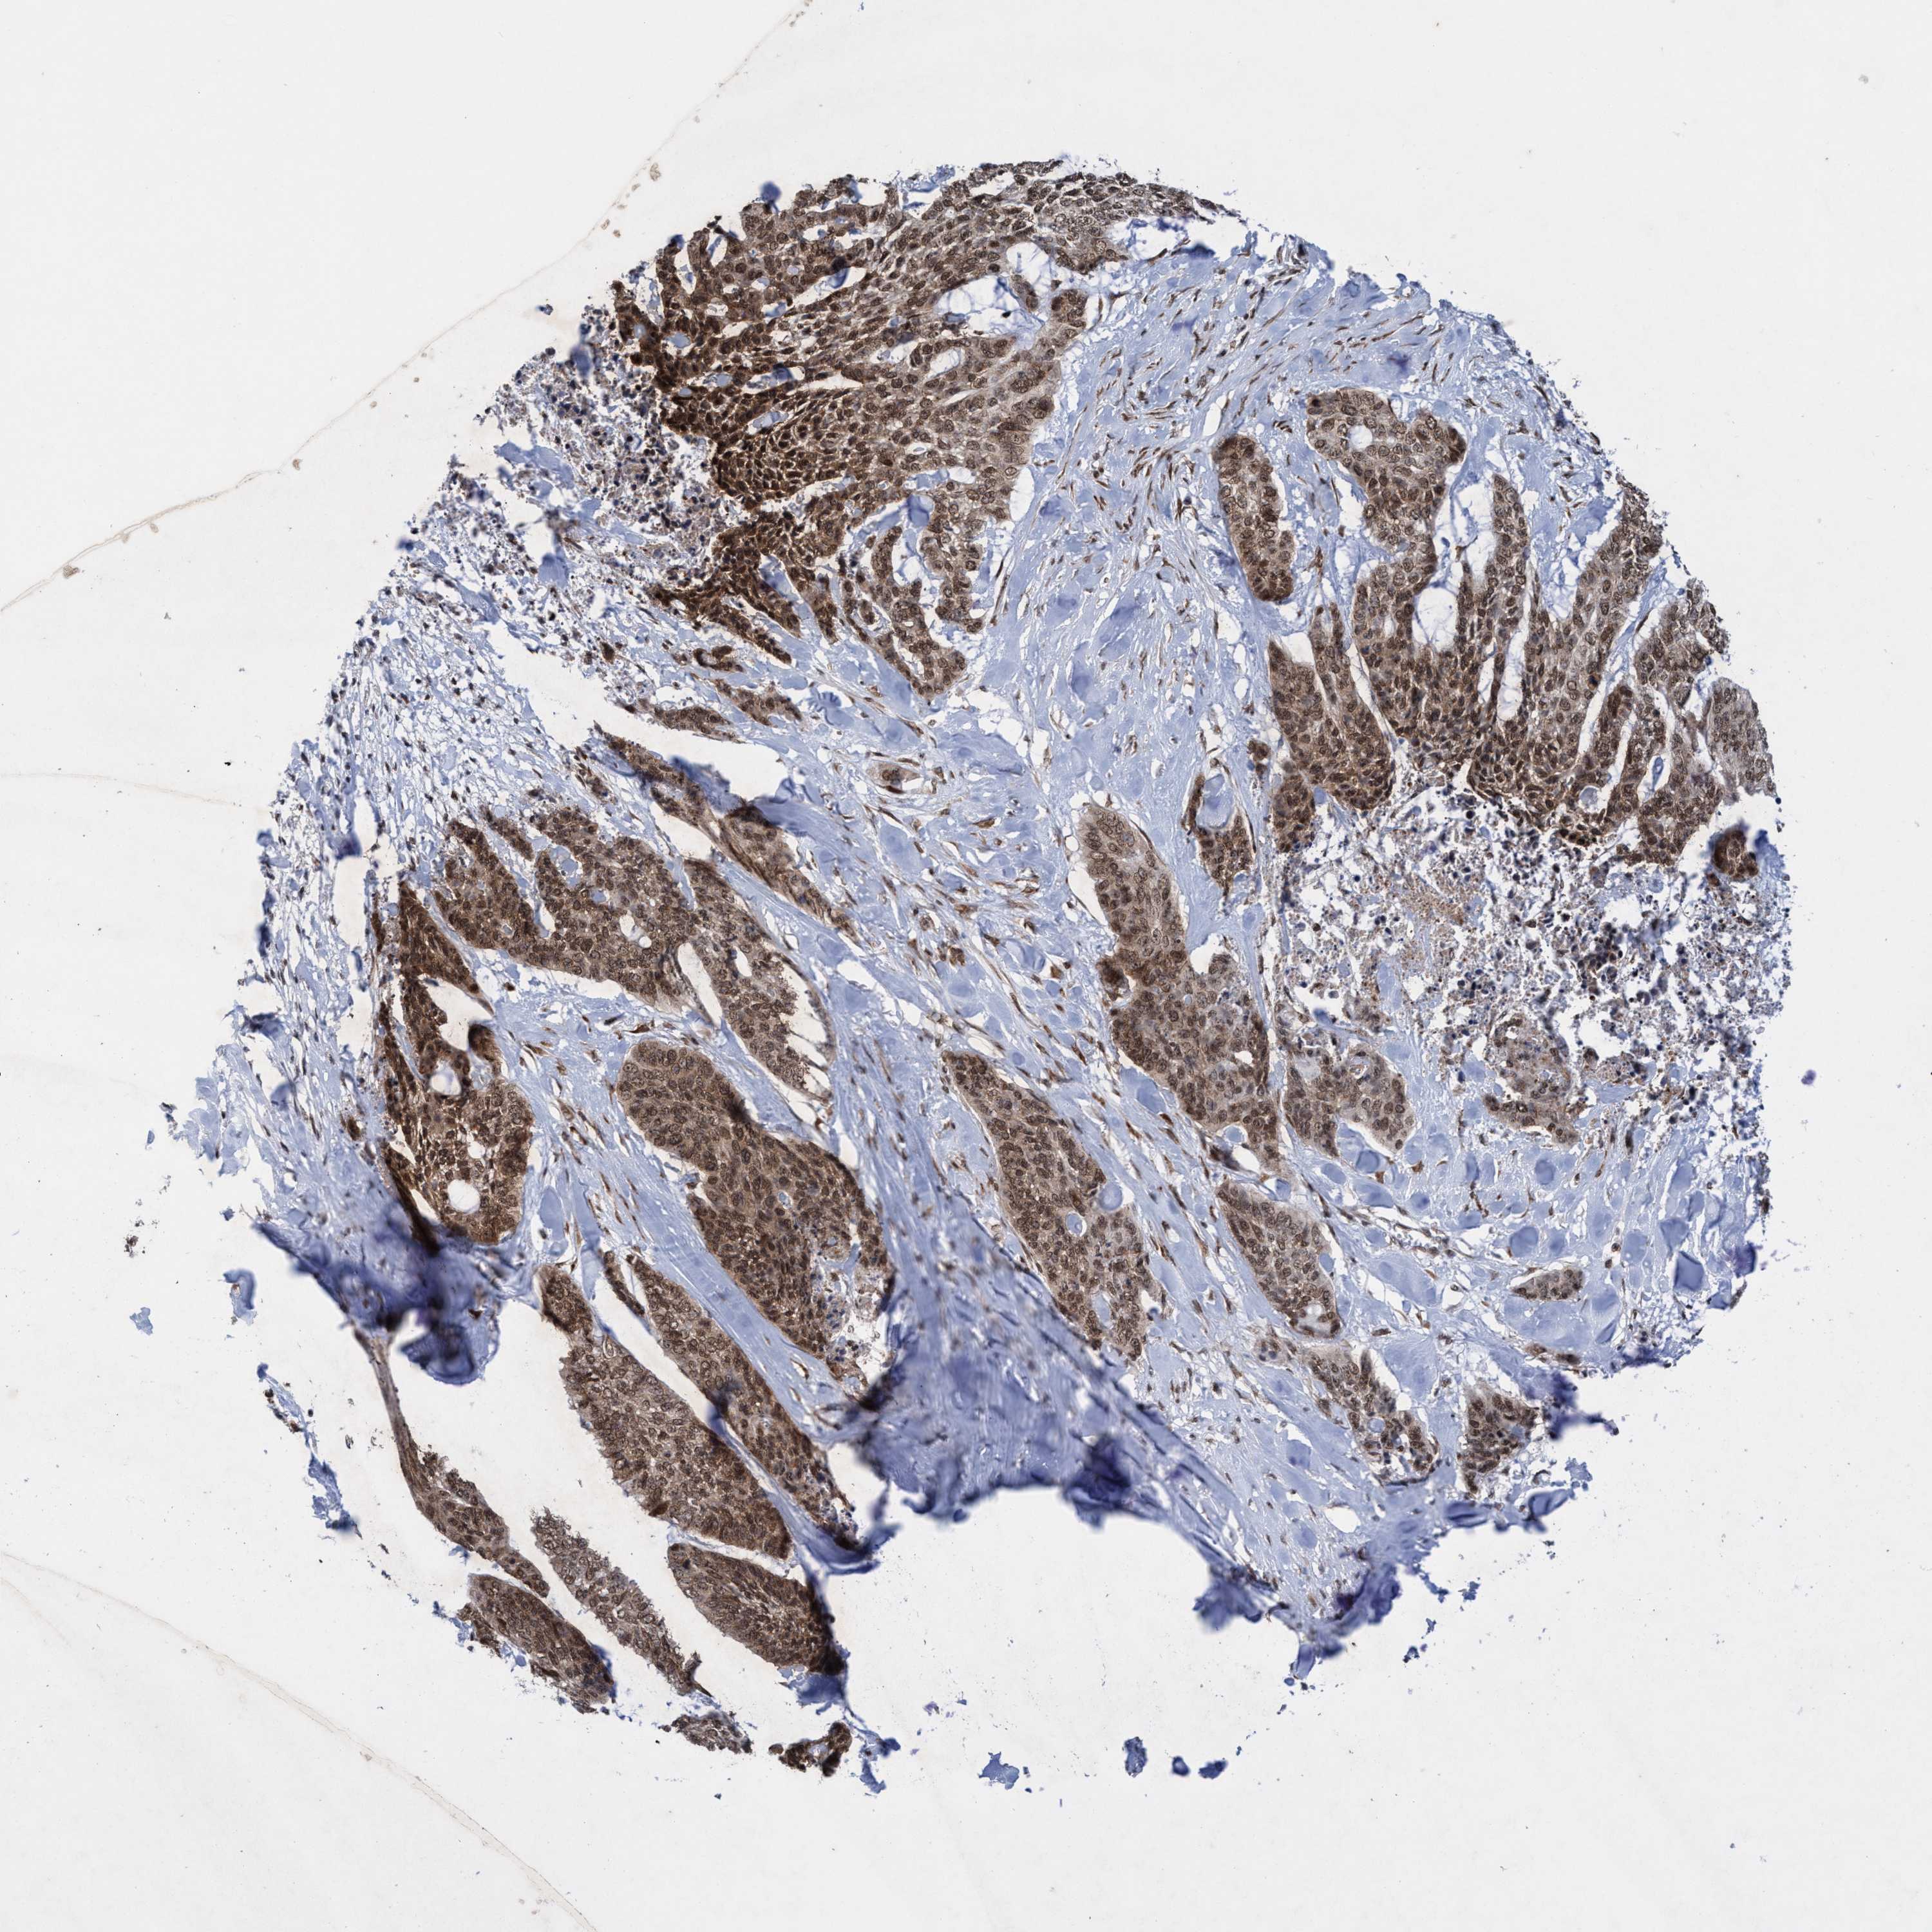

Basal cell and squamous cell cancer

SKIN CANCER - Protein expressioni

A mouse-over function shows sample information and annotation data. Click on an image to view it in a full screen mode. Samples can be filtered based on level of antibody staining by selecting one or several of the following categories: high, medium, low and not detected. The assay and annotation is described here.

Antibody stainingi

Antibody staining in the annotated cell types in the current human tissue is reported as not detected, low, medium, or high, based on conventional immunohistochemistry profiling in selected tissues. This score is based on the combination of the staining intensity and fraction of stained cells.

Each image is clickable and will lead to virtual microscopy that enables deeper exploration of all samples and also displays staining intensity scores, fraction scores and subcellular localization as well as patient and tissue information for each sample.

Antibody HPA023424

Staining

High

Intensity

Strong

Quantity

>75%

Location

Nuclear

Basal cell carcinoma